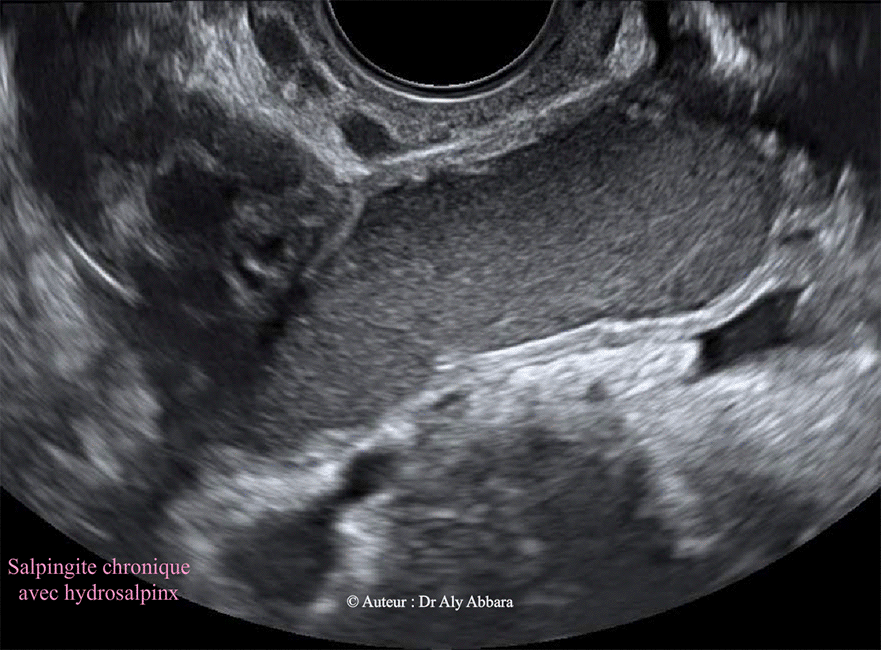

Salpingite chronique - Hydrosalpinx - Echographie

Image animée montrant l'aspect échographique d'une

salpingite chronique caractérisée par l'épaississement des parois tubaires et l'obstruction

de l'extrémité distale de la trompe à l'origine de la formation d'un volumineux hydrosalpinx